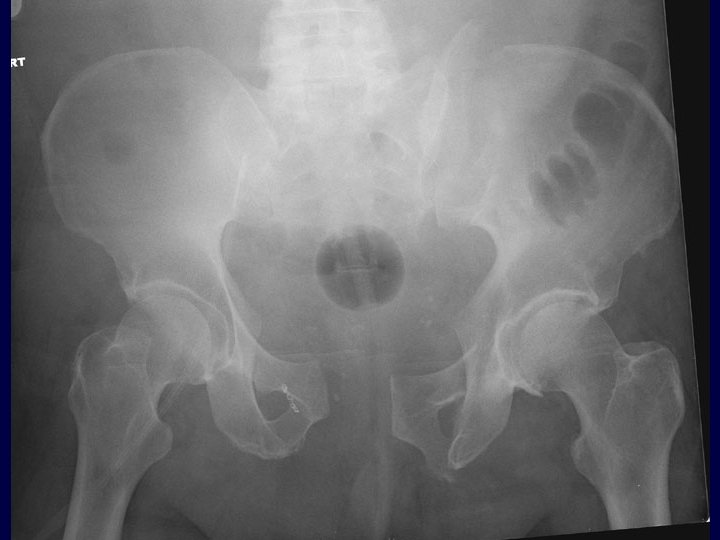

Immediate Percutaneous Fixation • From Chip Routt, MD